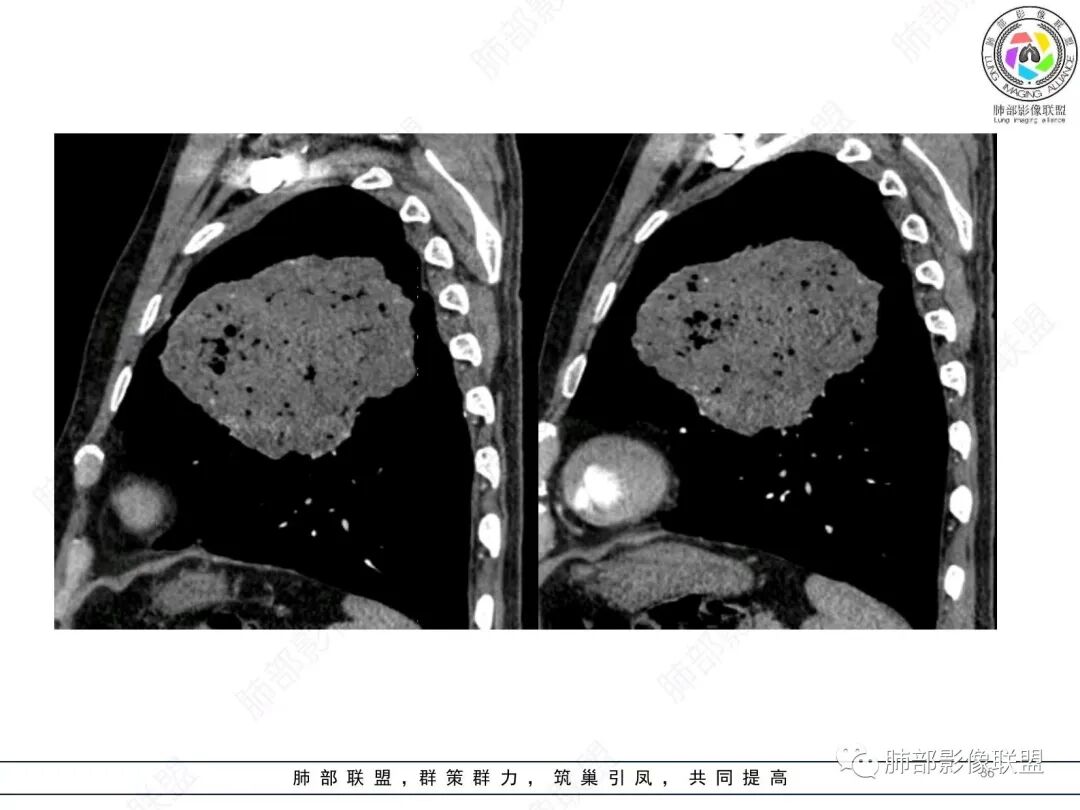

大肿块,边缘光滑,深分叶

近端支气管堵塞、推移为主

部分类似于脐凹征

内部支气管扩张

肺动脉推移为主,边缘部分进入

大肿块、表面光滑但深分叶,肺门侧支气管堵塞

回头看,内部支气管近端其实不连续,伴随肺动脉不存在

这两点就不符合

4)密度:肿块平扫为软组织密度,由于体积较大,内部常见大片状坏死,可出现不规则厚壁空洞或坏死内多发无壁小空洞,坏死多不均匀:坏死灶内可见如柳絮样的斑片样强化灶,坏死边缘与非坏死区分界不清本例坏死较明显,密度不均匀。

5)肿瘤强化方式:肺部恶性肿瘤强化程度与其血供丰富程度相关,血供丰富多强化明显,反之则较差。由于PSC 周边实性部分富血供及内部黏液变性、坏死,增强后肿块多数呈轻-中度边缘环形强化或不均匀小斑片状强化。国外学者对照病理发现肿瘤细胞或胶原组织增强扫描时强化,无强化的低密度区代表了黏液样变性区和出血坏死区。